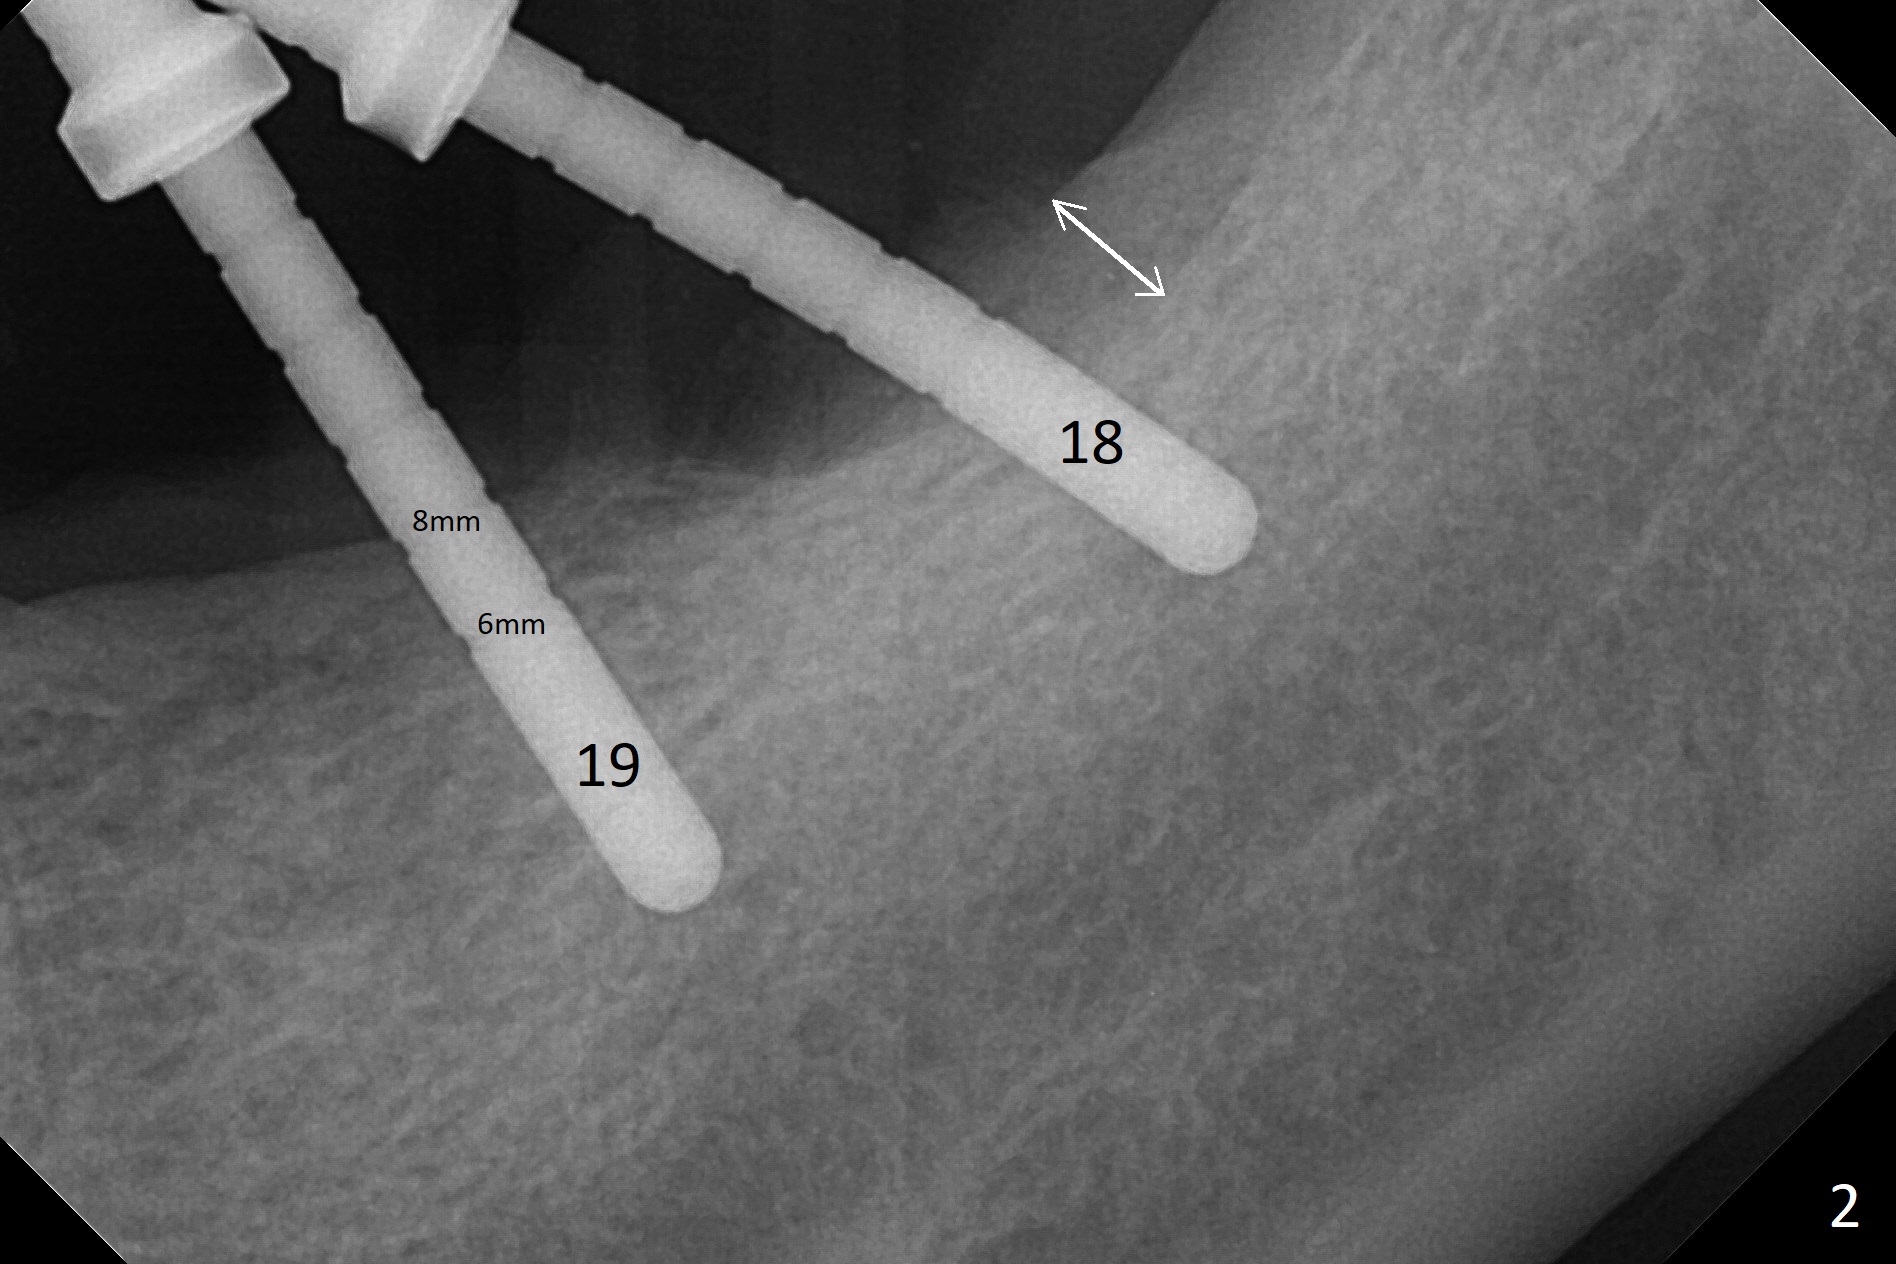

Preop photo shows severe mesial tilt of the tooth #18 (Fig.1). After extraction, the osteotomy is established in the apical end of the socket, where the buccolingual width is limited. It appears that an extra wide implant (5.9 mm) may perforate one of buccolingual plates. On the other hand, the buccal plate (Fig.2 double arrows) is intact and approximately 2 mm tall, whereas the lingual one is thin and lower. Initial osteotomy confirms that bone heights at #18 and 19 are 6 and 8 mm, respectively. Counting 2 mm of the buccal plate and bone graft lingually, a 8 mm long implant may be a practical option at the site of #18. After initial placement of two of 5x8 mm SM implants (Fig.3), the depth of the implant at #19 is adjusted twice (Fig.4,5). With placement of autogenous and allograft (Vanilla, Fig.5 *)) and abutments, a piece of cotton pellet is placed in each abutment well (access, Fig.6 *). Periodontal dressing is applied to the abutment wells for additional retention (Fig.7 *). Due to local poor oral hygiene, splinted provisional is fabricated 4 months postop (Fig.8) in preparation for limited orthodontic uprighting the tooth #20. The patient has pain with mastication at #18 eleven months post cementation (Fig.9). It appears that both of the implants should be removed with immediate replacement and bone graft. Prepare 4 PRF and sticky bone. The new implant will be 5.0 or 5.5x5 mm (Fig.10 green) with 2.3 mm platform (white). A block graft will be harvested from the ipsilateral ramus using 9/8 and 6/5 mm trephine burs for 2-3 mm in depth (Fig.11 blue). The ring graft will be seated around the platform over the implant (Fig.12).